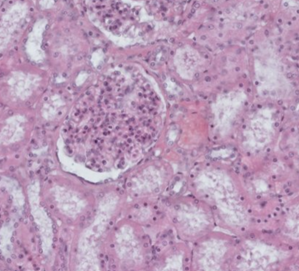

A 30-year-old woman suffered a serious contusion

of her left lower extremity while working on a local construction site.

Unfortunately, rhabdomyolysis occurs, which is characterized by the breakdown

of skeletal muscle tissue and the release of its contents, including myoglobin,

into the bloodstream. Myoglobin is a risk to the kidneys, especially when

present in high concentrations in the bloodstream. It fills the renal tubules

in the form of protein depositions and can lead to acute kidney injury. On the

second day of hospitalization, the patient experiences a decrease in urine

output. In addition, the serum creatinine level increases significantly.

Elevated serum creatinine levels indicate a decline in renal function because of

the physiological filtration of creatinine as a waste product. It should be

physiologically filtered by the kidneys and excreted from the body in the

urine. Its elevated levels are therefore a marker of impaired renal function.

The picture shows an image of a renal biopsy obtained. Which of the labelled

parts is primarily used to monitor the osmolarity of tubular fluid?